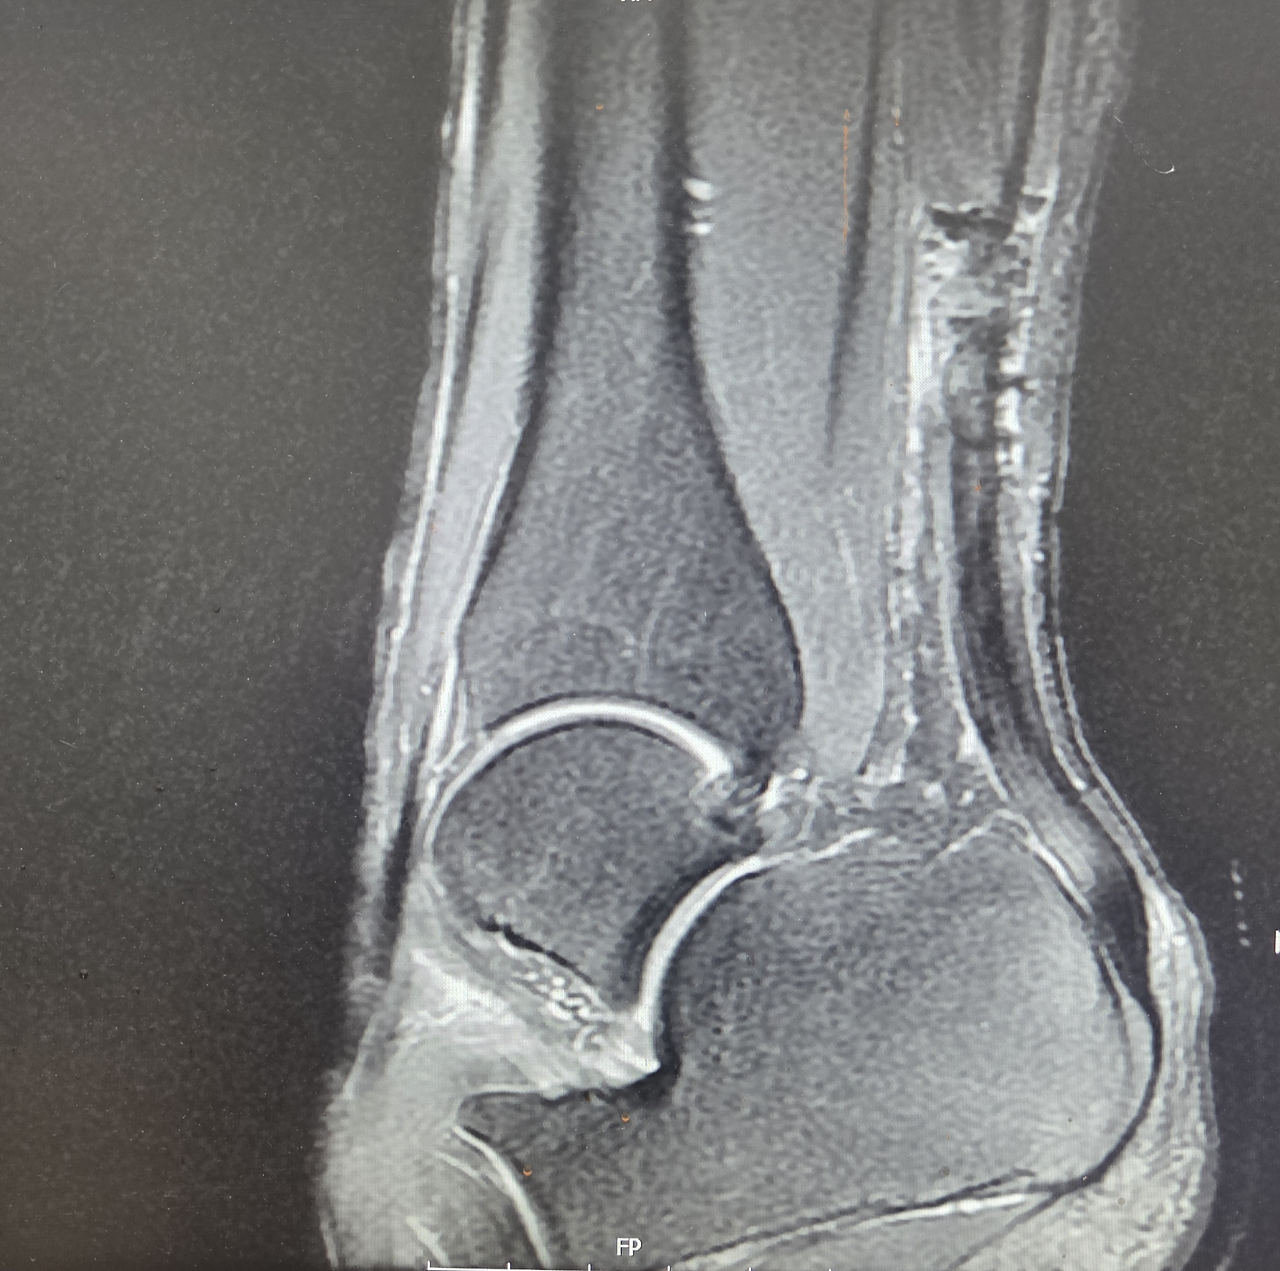

20대 초반의 남자 환자로 농구를 하던 도중 발목에서 “뚝” 하는 소리를 들은 뒤 심한 통증이 발생해 내원한 환자였다.

진찰 당시 아킬레스건 부위가 움푹 들어가 있었고 MRI에서도 완전 파열이 명확하게 확인되었다. 환자와 보호자에게 치료 방법과 이후의 과정에 대해 충분히 설명한 뒤 수술적 치료를 진행하기로 결정하였다.